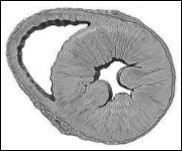

HFpEF, LV cavity typically has a normal volume and the walls are hypertrophic. See Figure 2. Histological examination shows the deposition of collagen and cardiomyocytes larger, stiffer than in HFrEF4. Despite the different cardiac structure and function, HFrEF and HFpEF hemodynamic patterns share similarities as well as differences. The clinical symptoms, renal dysfunction, neurohormonal activation, response to exercise and clinical findings may overlap10 However, increased ventricular and vascular stiffness can play a greater role than a real volume overload, in HFpEF compared with HFrEF. Thus, these two forms of IC are two well differentiated entities, with different pathophysiology and therapeutic approaches accordingly.

Figure 2.Model of concentric left ventricular hypertrophy, common in HFpEF.